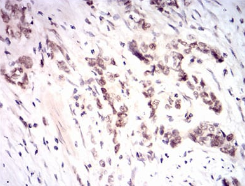

IHC    1/200 - 1/1000